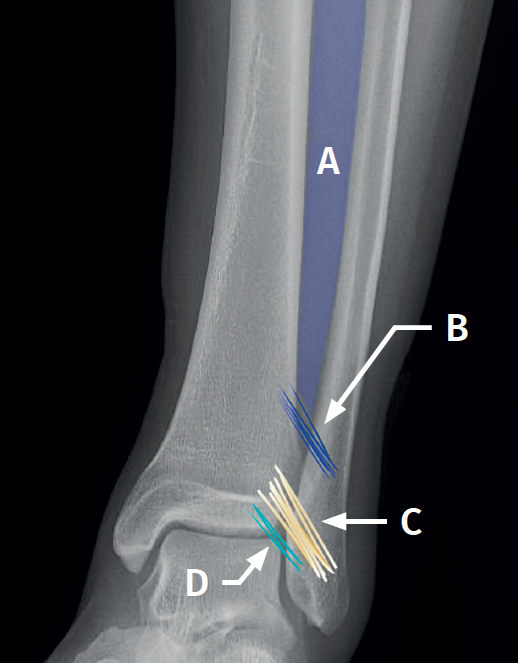

Figure 1. Schematic representation of the anterior syndesmosis. A: interosseous membrane; B: interosseous ligament; C: anterior tibiofibular ligament; D: distal fascicle of the anterior tibiofibular ligament.

Syndesmosis (Figure 1)

The syndesmosis is a fibrous ring that joins the tibia and fibula distally(1). Its main function is to maintain the congruence of the tibiofibular mortise and to allow physiological micromovements of separation and rotation of the fibula with respect to the tibia(6).

It is composed of:

- The anterior tibiofibular ligament (ATFL). Considered to be the first to be injured by external rotation or forced dorsiflexion forces. It extends obliquely from the anterior tubercle of the distal tibia, approximately 5 mm above the joint surface, to the anterior tubercle of the distal fibula, running proximal-medial to distal-lateral and crossing the anterolateral corner of the talus(7).

- The ATFL has a constant distal fascicle (ATFL-DF) that contacts the anterolateral corner of the talus when the ankle is in neutral position. The distal fibers of the ATFL-DF continue with the upper bundle of the anterior talofibular ligament(8).

- The posterior tibiofibular ligament (PTFL), which is stronger than the anterior ligament. It extends from the posterior tibial malleolus to the posterior tubercle of the fibula and runs proximal-medial to distal-lateral. It forms an angle of 20º to40° with the horizontal plane.

- The interosseous ligament (IL), a distal thickening of the interosseous membrane that acts as a "spring" or dynamic stabilizer.

- The transverse ligament, located in the most posterior part, and considered by some authors as the distal portion of the PTFL.